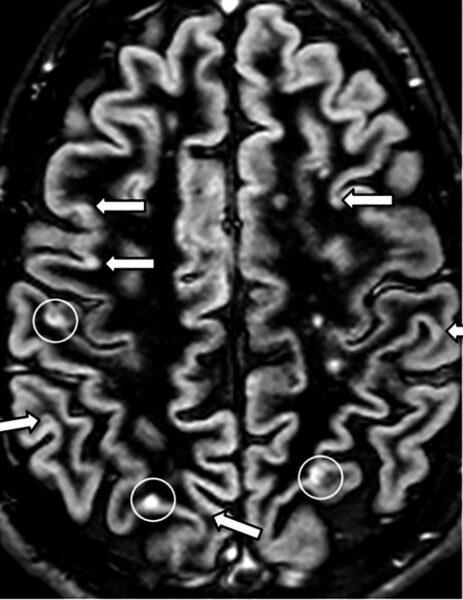

Scleroza multiplă este o boală neurologică inflamatorie cronică în care sistemul imunitar poate afecta mielina care învelește fibrele nervoase. Evoluția și manifestările sunt variabile: unele persoane au perioade de exacerbare urmate de remisiuni, altele un curs progresiv. Există simptome frecvente (oboseală, probleme de vedere, amorțeli, tulburări de mers) și semnale care impun consult imediat, precum pierderea bruscă a vederii, slăbiciunea rapidă a unei părți a corpului sau tulburările acute de vorbire și echilibru.

Cercetarea susține ideea că interacțiunea dintre factori genetici și factori de mediu (infecții anterioare, vit D, fumat etc.) contribuie la risc. Procesele imunologice implică celulele T și B, inflamație și consecințe neurodegenerative. Există tratamente aprobate care pot modifica evoluția bolii, dar multe întrebări rămân: de ce unii răspund bine la tratament, cum se previne progresia pe termen lung și în ce măsură intervențiile complementare pot influența calitatea vieții.